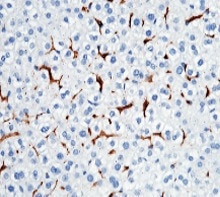

Anti-CD64 antibody. Rabbit monoclonal. Cat#: 50086-R001.

Immunochemical staining of mouse CD64 in mouse liver. Image Credit: Sino Biological Inc.